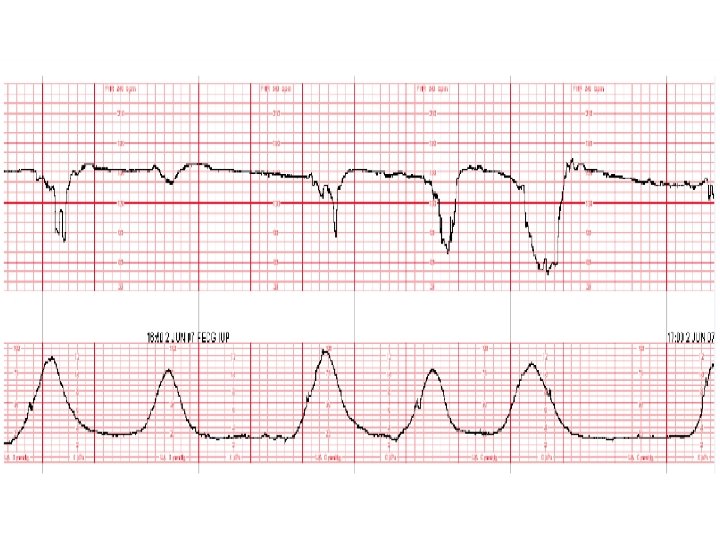

Variable Deceleration Abrupt decrease in FHR of > 15 beats per minute measured from the most recently determined baseline rate. The onset of deceleration to nadir is less than 30 seconds. The deceleration lasts > 15 seconds and less than 2 minutes. A shoulder, if present, is not included as part of the deceleration. Variable decelerations may be observed in up to 50% of NSTs. If nonrecurrent and <30 seconds, they are of no clinical significance.

Variable Deceleration Typical: • shoulders Atypical : • Overshoot • Loss of primary shoulder • Slow return to baseline (late component) • Baseline returns to a lower level(after deceleration) • Biphasic(W shape) • loss of variability during deceleration

Classification severity of variable deceleration • Mild: duration < 30 second or depth up to 80 bpm • Moderate : deceleration < 80 bpm • Severe : deceleration < 70 bpm for more than 60 second

Causes of cord compression pattern • • Oligohydramnious Dilatation 8 -9 cm Rapid descending True umbilical cord prolapse(rare)

Complicated variable deceleration Indicated fetal hypoxia • Tachycardia • Lack of variability • Slow return to baseline • Large amplitude(to 60 bpm or duration 60 second) • Loss of pre and post shouldering • Smooth overshoot